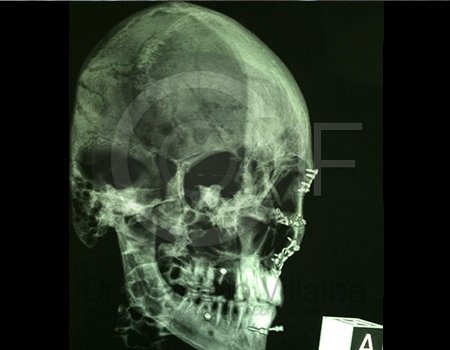

Fractura de Malar

Fractura De Malar2 Post